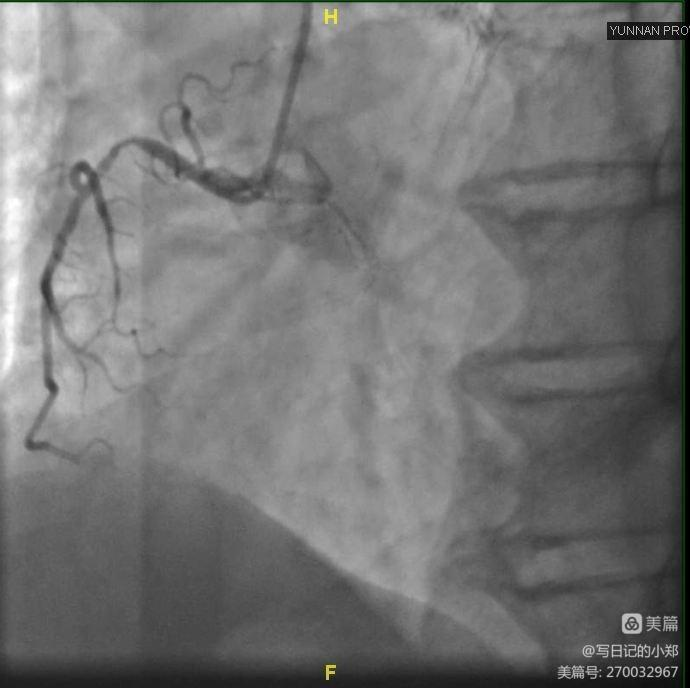

2022年10月6日,来自云南省大理州70岁的常老爷子,因为心脏冠状动脉多支血管重度狭窄到我院就诊,冠脉造影提示:前降支近端狭窄70%。中段支架内狭窄70%,第一对角支开口狭窄70%,回旋支中段狭窄99%,远端狭窄90%,第一钝缘支狭窄65%。右冠状动脉近端狭窄85%;

心脏彩超:左心室扩大(LVDD57mm),节段室壁运动异常;动态心电图检查发现频发室性过早搏动,呈二联律;主动脉CT:主动脉多发溃疡板块形成。